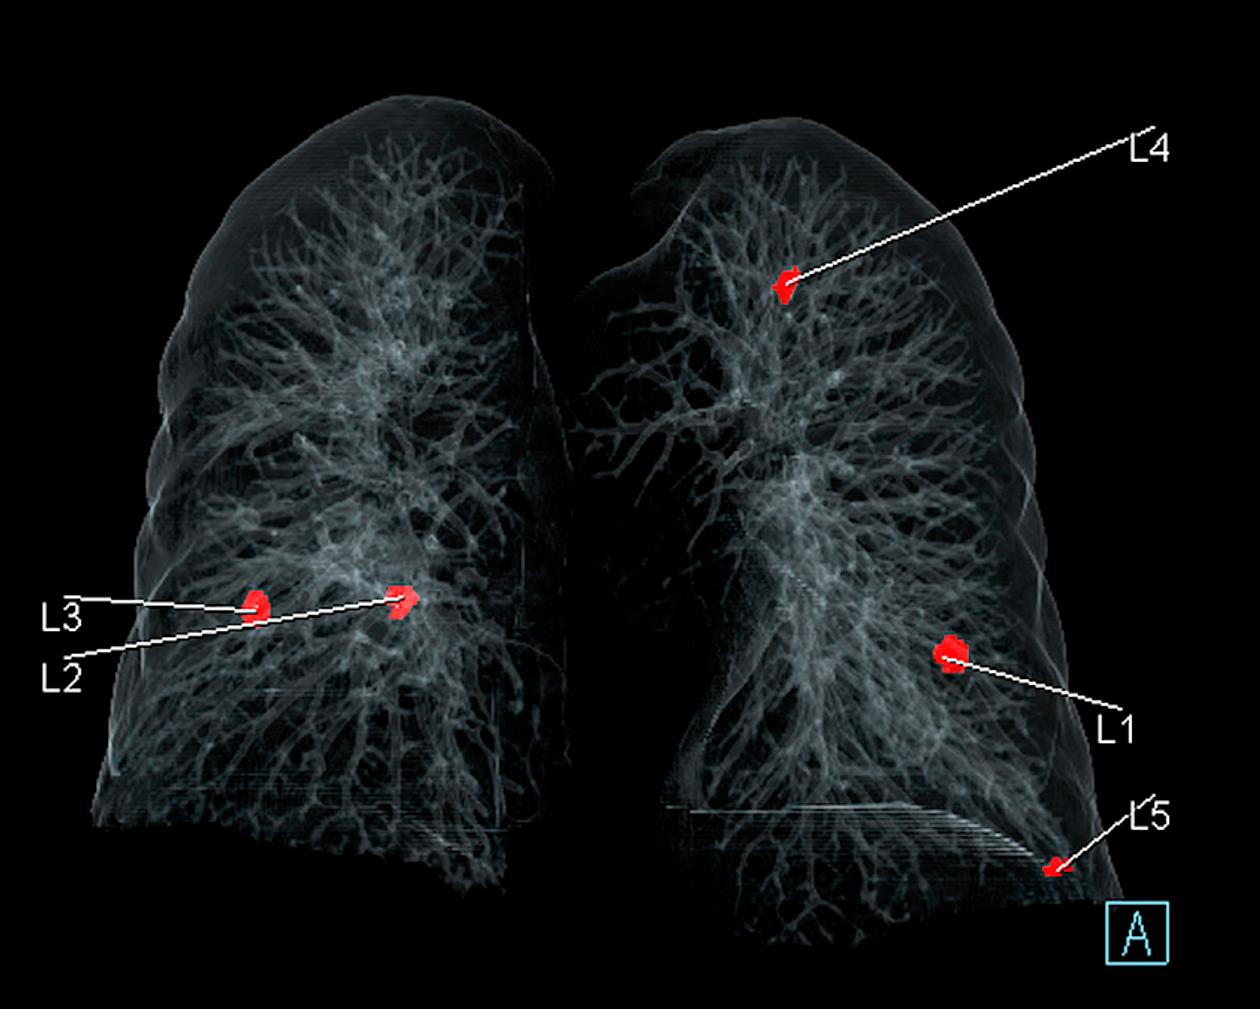

Détection de nodules pulmonaires cancéreux par l’IA au scanner, à l’hôpital Foch. HOPITAL FOCH

Cela n’empêche cependant pas l’hôpital de continuer sa politique volontariste. L’IA est utilisée pour dépister les nodules pulmonaires depuis 2021 et en mammographie depuis janvier 2022. Un logiciel pour détecter l’embolie pulmonaire est actuellement en évaluation. « Nous sommes sur la courbe dite “de Gardner” : toute révolution technologique connaît, dans son utilisation, une période d’euphorie, une pente de la désillusion, avant de trouver un niveau asymptotique correct d’utilisation. Nous sommes dans une certaine désillusion, mais cela va évoluer. Entre-temps, nous devons nous approprier ces outils, nous acculturer pour bien inclure cette brique dans le work flow [“flux de travail”] », affirme-t-il.

Alors que « beaucoup de solutions d’IA sont proposées sans performances cliniques validées en France », continue Isabelle Thomassin, une initiative, Drim France IA, a été lancée par le Conseil national professionnel de la radiologie (qui rassemble radiologues libéraux, universitaires, hospitaliers et sociétés savantes) afin de clarifier la situation et d’aider les radiologues à s’y retrouver. Cette association de loi 1901 a sollicité les start-up éditrices afin de « répondre à une grille analytique et descriptive de leurs solutions pour les aides au diagnostic de cancer du sein, de fractures osseuses et de nodules pulmonaires, qui constituent la majorité des logiciels proposés sur le marché français ». Des démarches similaires, portées respectivement par l’American College of Radiology et la Canadian Association of Radiologists sont en cours aux Etats-Unis et au Canada.